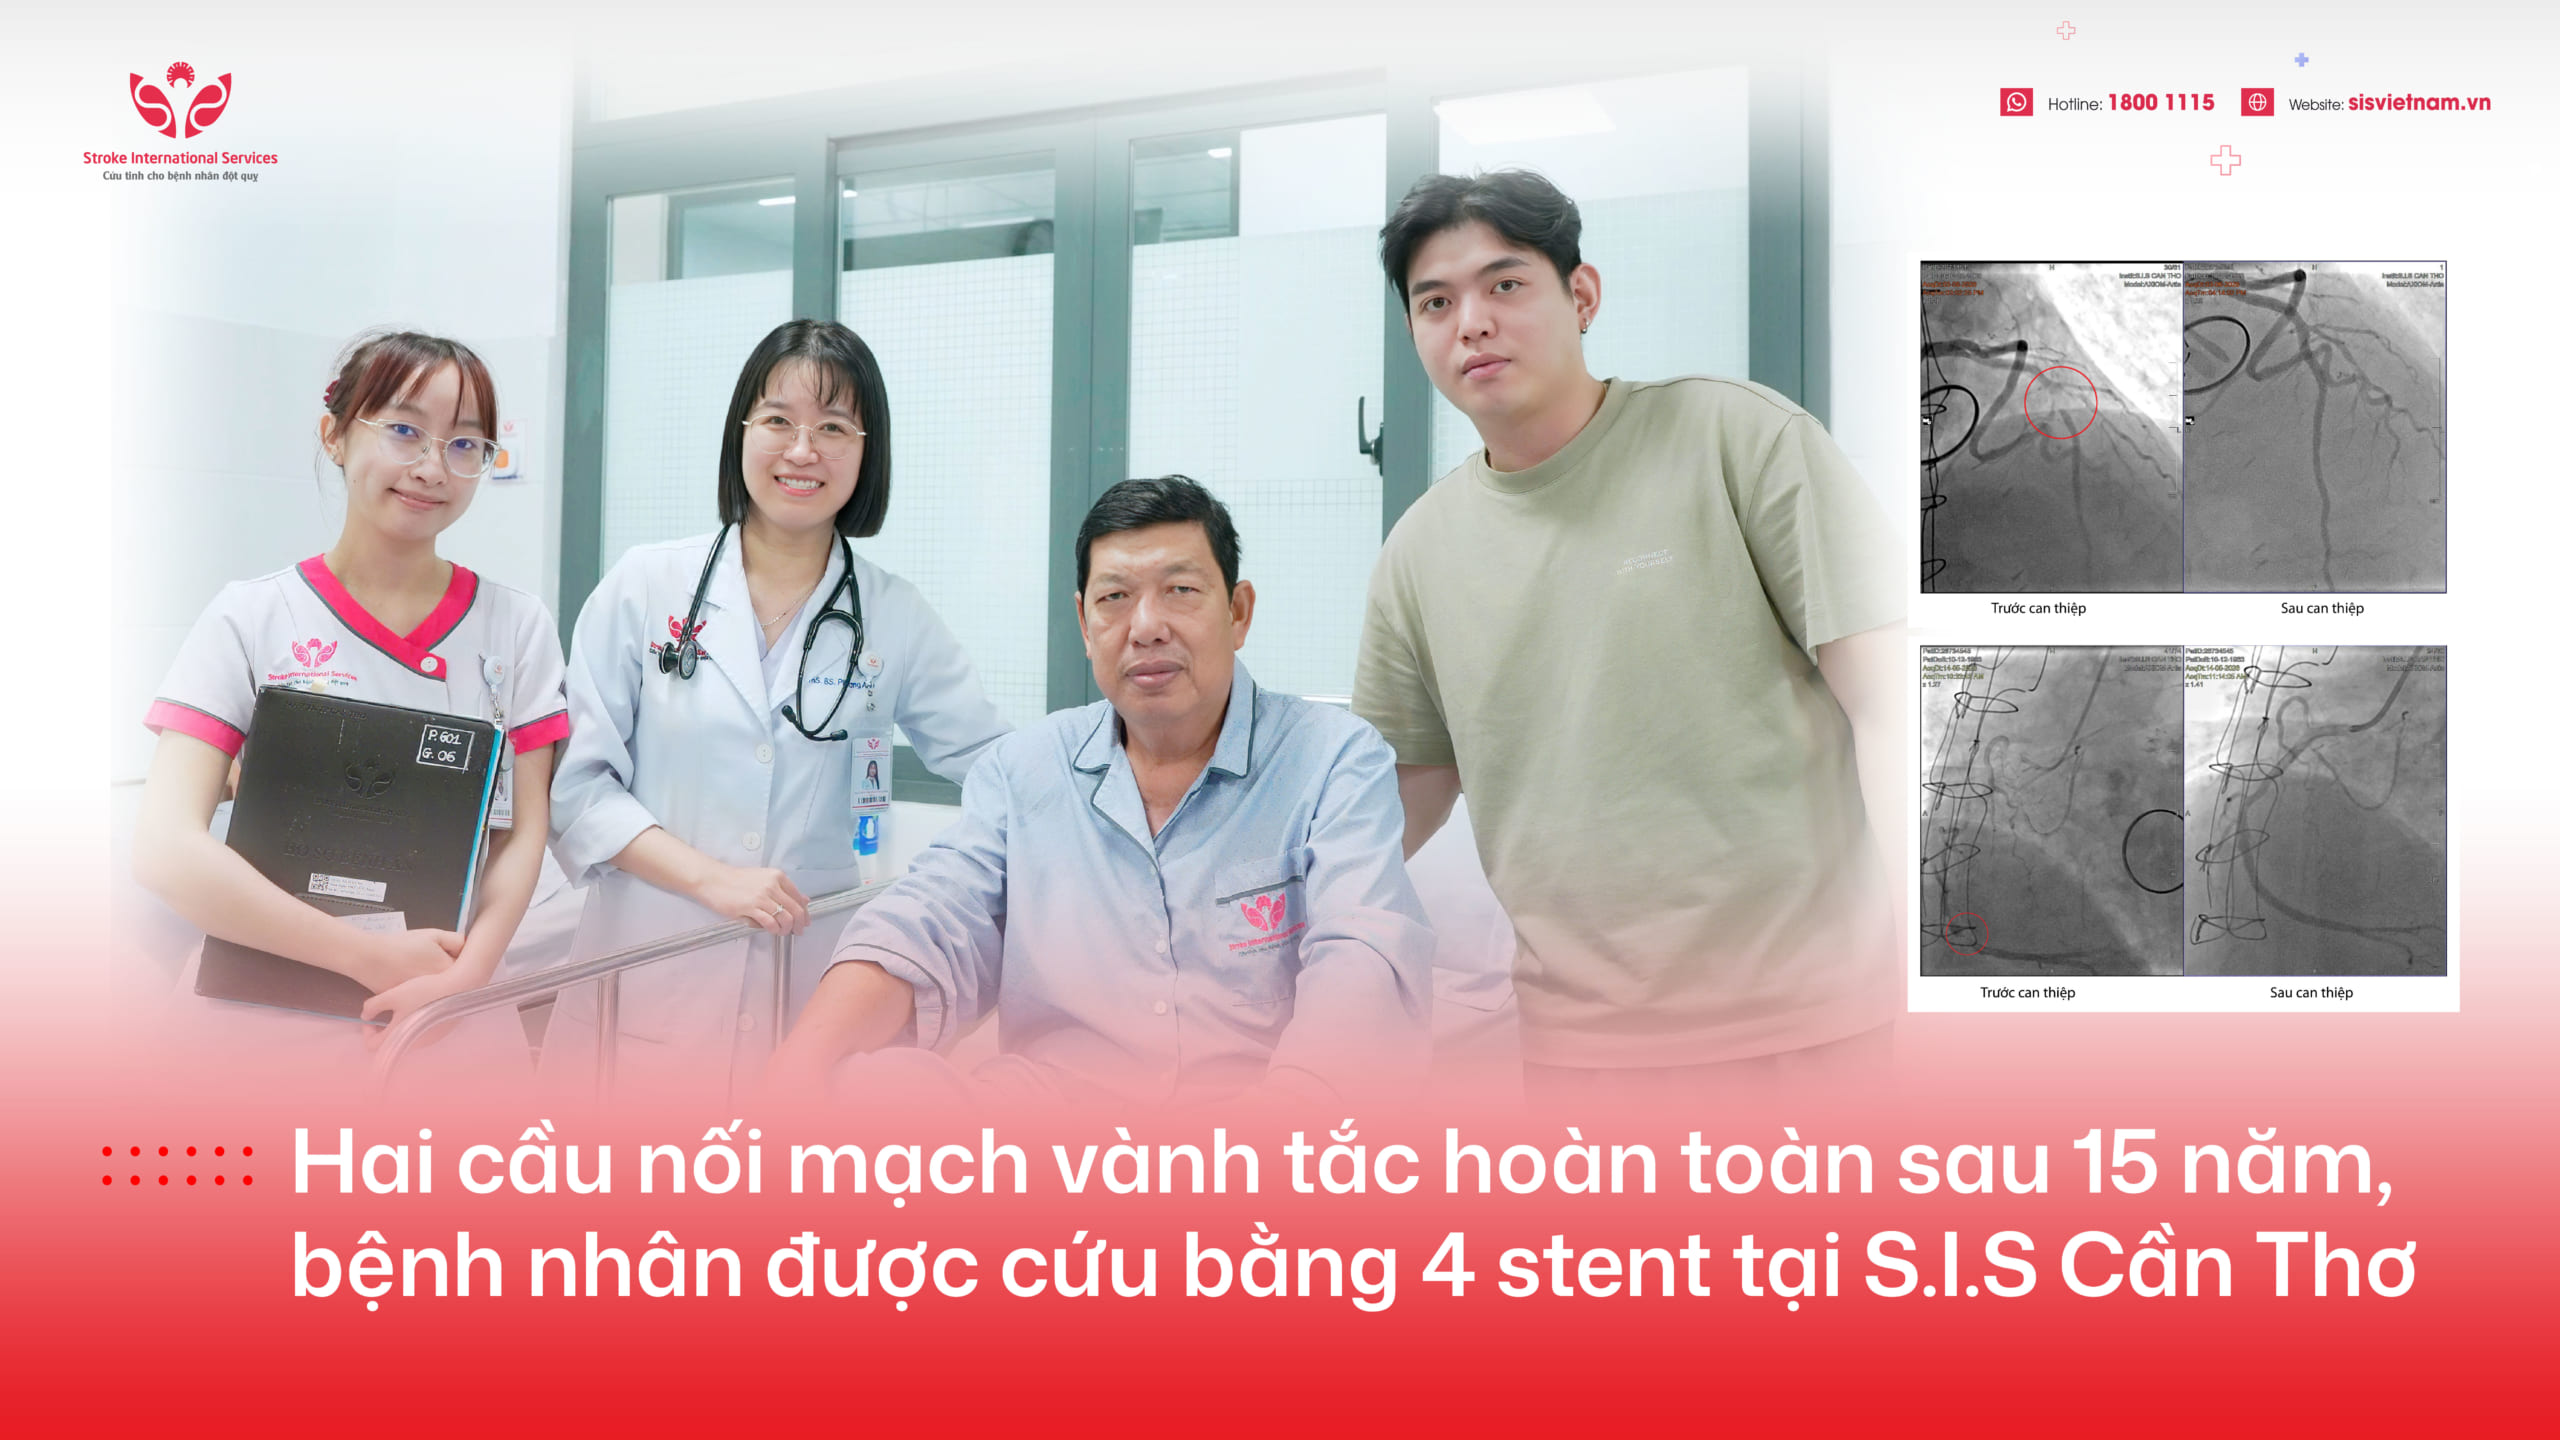

Vừa qua, Bệnh viện ĐKQT S.I.S Cần Thơ đã cấp cứu và điều trị đột quỵ thành công cho bệnh nhân nam P.P (47 tuổi) người Campuchia. Đây là ca đột quỵ hiếm hoi may mắn được người nhà đưa từ Campuchia đến S.I.S Cần Thơ cấp cứu còn trong khoảng thời gian vàng.

Ekip đã tiến hành can thiệp hút huyết khối, nhưng sau đó không tái thông được. Chúng tôi phải dùng đến phương pháp cuối cùng là nong mạch máu cho bệnh nhân mới tái thông lại được. Sau can thiệp, bệnh nhân phục hồi tốt. Đến ngày xuất viện bệnh nhân đã tỉnh táo, ăn uống được, đã nói lại được nhưng chưa linh hoạt. Về sức tay chân của bệnh nhân đã có thể cử động nhẹ.

Bệnh nhân ở Campuchia nhưng may mắn được người nhà đưa đến S.I.S Cần Thơ trong thời gian vàng. Đây là điều đáng hoan nghênh! Cho thấy sự nỗ lực của người nhà và kiến thức cộng đồng về đột quỵ đang được nâng cao”.